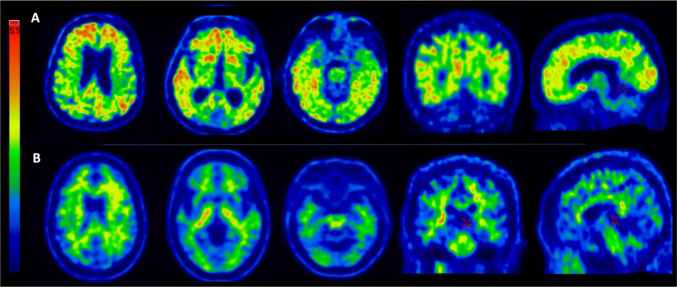

Abstract Image